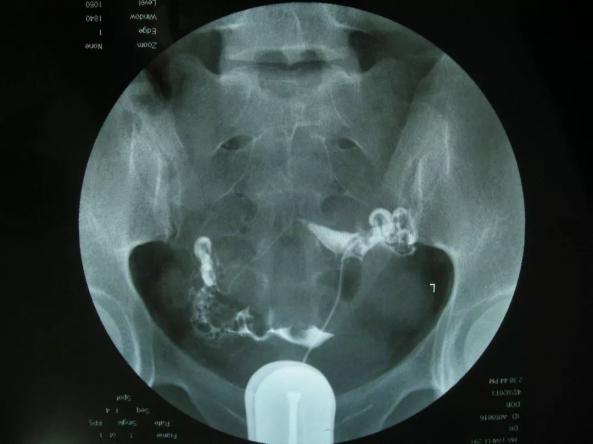

心電圖:肺栓塞的心電圖有特征性表現,導聯出現S波,導聯出現Q波及T波倒置。動脈血栓是腦梗的根源,靜脈血栓則是“隱形殺手”,如深靜脈肺栓塞。肺栓塞檢查需要查哪些項目肺栓塞又稱急性肺血栓栓塞,通常需...